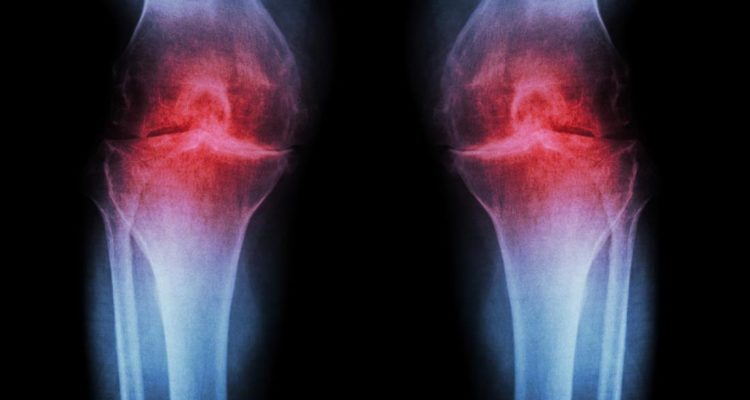

Учені з Гарвардської медичної школи назвали 5 причин виникнення артрозу. Фахівці відзначили, що захворювання супроводжується ураженням хрящової тканини суглобів.

Однією з причин хвороби є неправильна техніка бігу. Неприємні відчуття можуть виникати в результаті зношених або розірваних хрящів, напруг в сухожиллях і подразнень м’яких тканин. За словами лікарів, існує поняття “коліно бігуна”, яке має на увазі патології у вигляді болю в області колінної чашечки.

Наступною причиною артрозу може бути ожиріння. Зайві кілограми надають серйозне навантаження на суглоби, що є загрозою для людей з надмірною вагою. Лікарі рекомендують таким пацієнтам відмовитися від важких фізичних вправ і зайнятися скандинавською ходьбою і плаванням. Недолік рідини теж становить небезпеку для колін. Суглобова сумка виділяє менше синовіальної речовини і це впливає на функцію змащення, зменшує тертя між елементами суглобів.

Із захворюванням пов’язані надмірні навантаження, особливо потрібно бути обережним новачкам в спорті. Виконання складних вправ може спровокувати зсув колінної чашечки, вивих колінного суглоба і навіть переломи. Фахівці радять добре розминатися перед тренуванням і не забувати про відпочинок між підходами. Холодні температури також збільшують ризик захворювання, тому потрібно тепло одягатися і не допускати переохолодження.